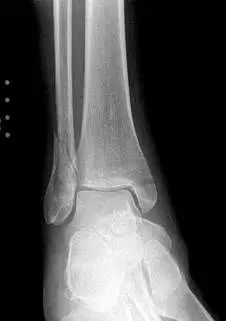

Both the lateral and medial malleolus with fractures with the lateral malleolar fracture classified as a Weber B (at the level of the ankle joint) and the medial malleolar fracture almost transverse (Left x-ray). This is indicative of a Supination External Rotation (SER IV) injury. The fractures are repaired using open reduction with internal fixation (ORIF) technique and fixated with screws and a surgical fractue plate located at the fibular (Right x-ray).

A bimalleolar fracture is a fracture of the ankle that involves the lateral malleolus and the medial malleolus. Studies have shown that bimalleolar fractures are more common in women, people over 60 years of age, and patients with existing comorbidities. Surgical treatment will often be required, usually an Open Reduction Internal Fixation (ORIF). This involves the surgical reduction or realignment of the fracture followed by the implementation of hardware to aid in the healing of the fracture. Usually a plate and screws will be used on the fibular fracture and screws, screws and pins, pins or tension band will most commonly be used on the medial malleolus fracture. A bimalleolar "equivalent" fracture is a fracture of the fibula with rupture of the superficial and deep portion of the deltoid ligaments leaving the medial malleolus intact. Surgical management is common due to the instability of the fracture and displacement of the talus laterally.

The x-ray images below demonstrate another case of a bimalleolar ankle fracture in both and oblique view (left) and anterior - posterior view (right).